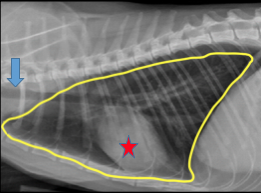

(3) Thoracic radiographs

Why? Thoracic radiographs depict Sparta’s heart and lungs. The size of the heart can be measured; an enlarged heart size suggests disease. The appearance of the lungs on the radiograph can help us pinpoint where the problem is in the lungs and what it may be.

Results: Sparta’s heart was a normal size, but there was material in and surrounding the bronchi and bronchioles of his lungs. This material was plugging up his airways and preventing the passage of air into his lungs. His lungs were also hyperinflated, which was a consequence of trying to overcome the obstruction to breathe.

Sparta. The small white circles throughout his lungs are the inflamed small airways.